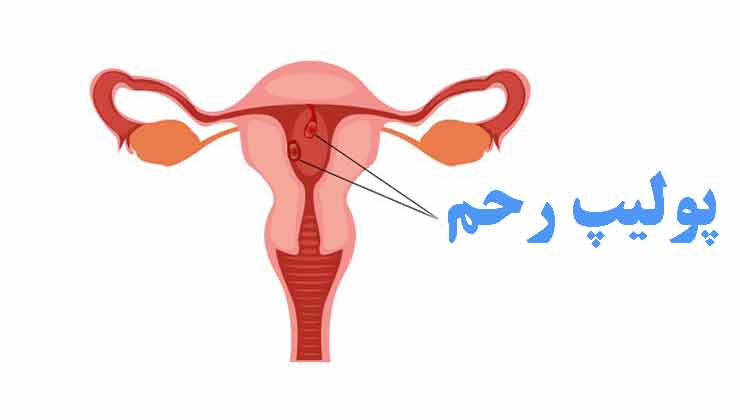

بهترین دکتر پولیپ رحم در اهواز + لیست 10 تایی